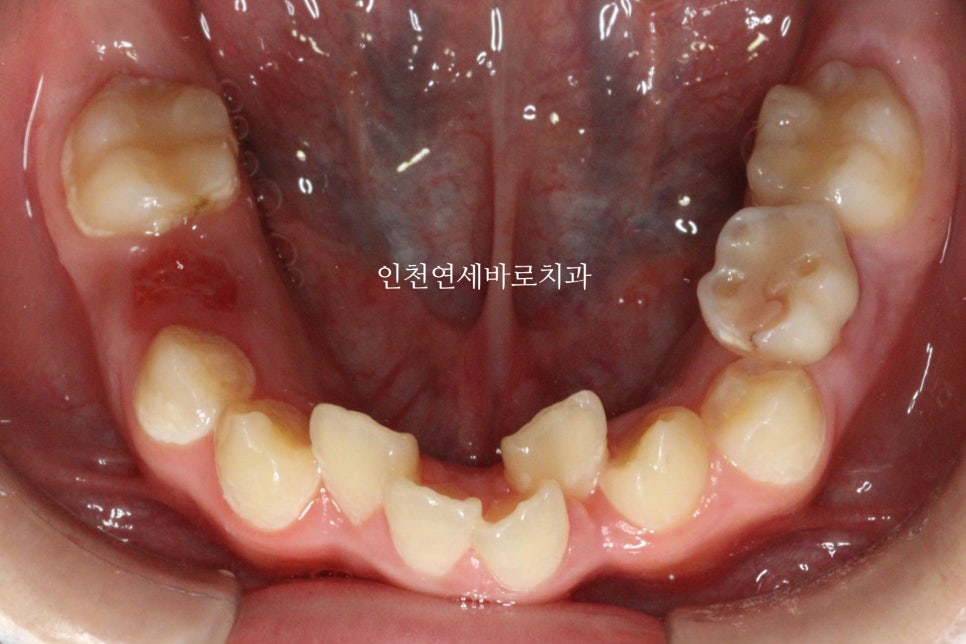

여러가지 이유로 남아있던 유치를 뺏습니다.

피가 조금 나서 흑백처리했습니다.